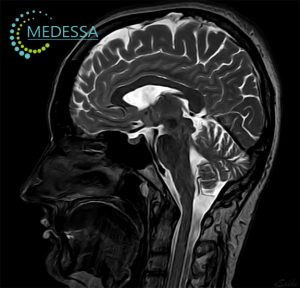

МРТ-діагностика в медичному центрі MEDESSA